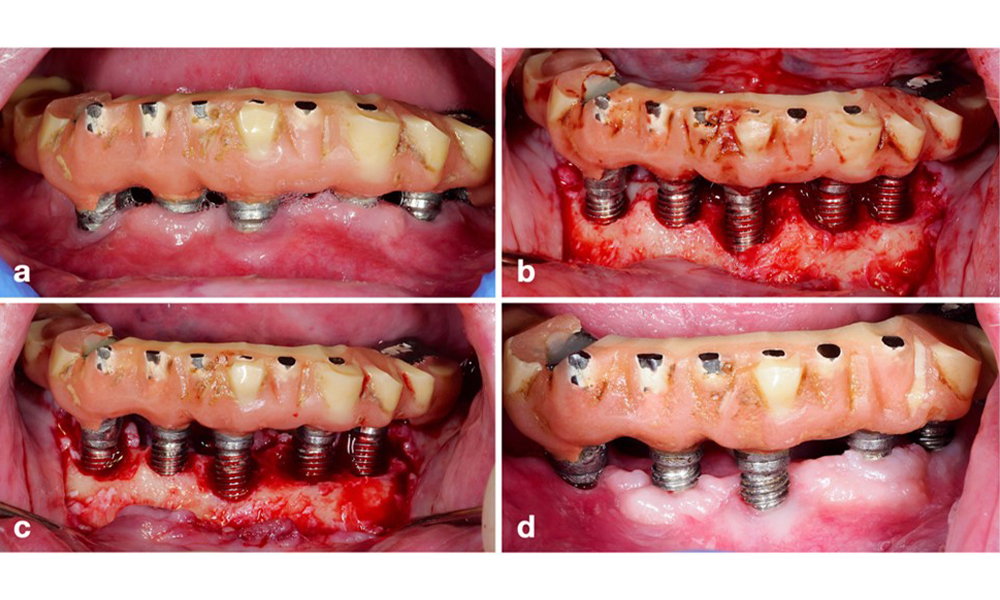

Thus, both the patient's oral hygiene routines and the prosthetic restoration’s design and implant positioning should support effective cleaning. If required, adjustments to the existing restoration (figure 5) and specific instructions for tailored oral hygiene measures are essential (figure 6) (Hamilton et al. 2023; Jepsen et al. 2015).

Modification of an existing bridge restoration. If the restoration hinders sufficient oral hygiene measures (notice the extreme overhang on the buccal aspect of the molar) (a–b), one of the first treatment steps should be adjusting the prosthetic design to enable effective cleaning (c–d).

Figure 5. Modification of an existing bridge restoration. If the restoration hinders sufficient oral hygiene measures (notice the extreme overhang on the buccal aspect of the molar) (a–b), one of the first treatment steps should be adjusting the prosthetic design to enable effective cleaning (c–d).